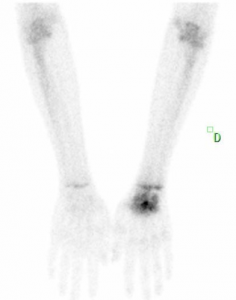

La scintigraphie osseuse SPECT montre un foyer hypervascularisé et hyperfixant focal du capitatum et un rehaussement diffus du reste de l’os et du carpe.

Ostéonécrose post traumatique du capitatum.